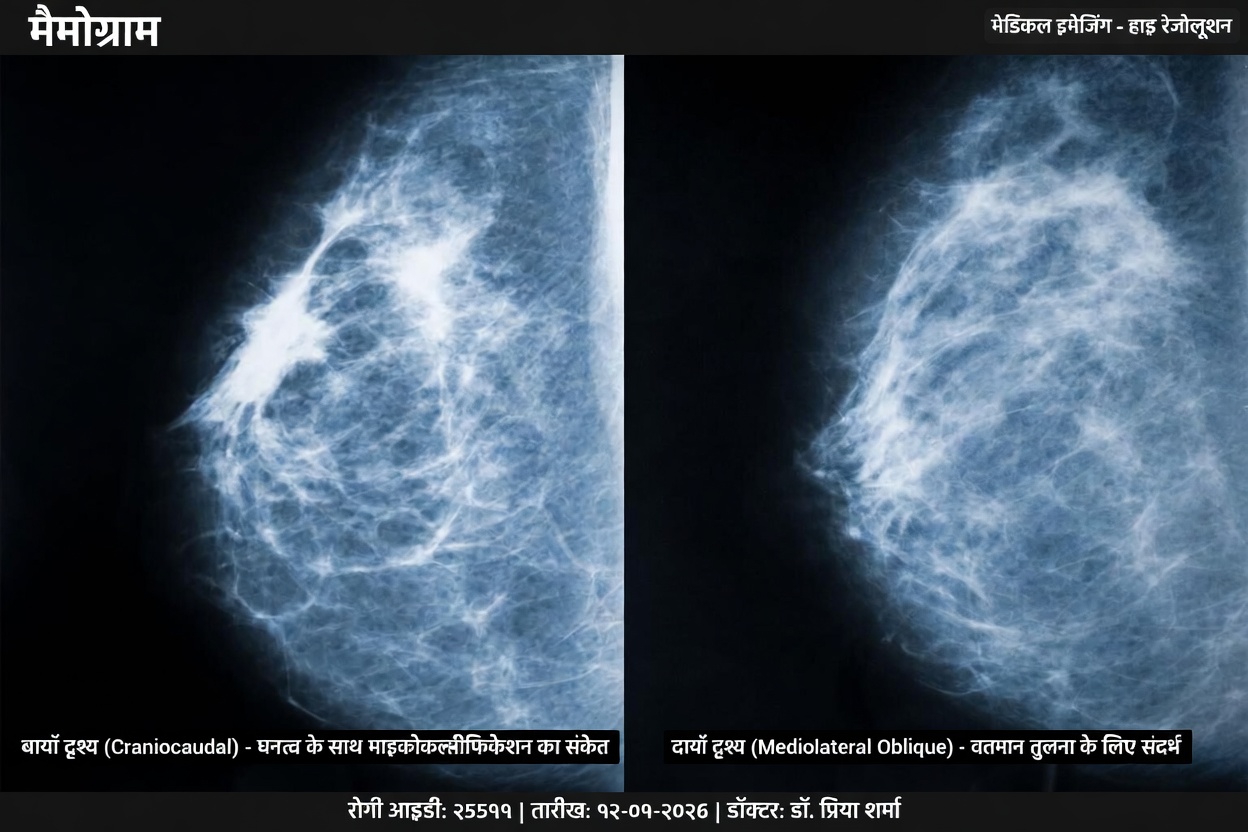

मैमोग्राम में घने ऊतक अक्सर सफेद रंग में दिखाई देते हैं। समस्या यह है कि कुछ असामान्यताएँ भी उसी तरह सफेद दिख सकती हैं। ऐसे में कभी-कभी इमेज की व्याख्या करना अधिक कठिन हो जाता है।

पारंपरिक मैमोग्राफी ऊतकों के बीच मौजूद कॉन्ट्रास्ट को पहचानकर काम करती है। वसायुक्त ऊतक इमेज में गहरे दिखते हैं, जबकि घने ऊतक हल्के या सफेद दिखाई देते हैं।

यदि कोई छोटा असामान्य क्षेत्र भी इमेज में हल्के रंग का दिखे, तो वह आसपास के घने ऊतक में मिल सकता है। इससे उसे स्पष्ट रूप से पहचानना कुछ मामलों में मुश्किल हो सकता है।

लेकिन रेडियोलॉजी संबंधी शोध यह संकेत देते हैं कि घने स्तन ऊतक वाली महिलाओं के लिए कभी-कभी स्क्रीनिंग रणनीति में बदलाव किया जा सकता है।

हाल के दो चिकित्सीय अध्ययनों ने यह समझने की कोशिश की कि घने स्तनों वाली महिलाओं में अतिरिक्त इमेजिंग तकनीकें किस तरह मदद कर सकती हैं।

निष्कर्ष उल्लेखनीय थे।

कुछ परिस्थितियों में, सप्लिमेंटल स्क्रीनिंग यानी अतिरिक्त जांच ऐसे बदलावों का पता लगा सकती है जो केवल मैमोग्राम में स्पष्ट रूप से न दिखें।